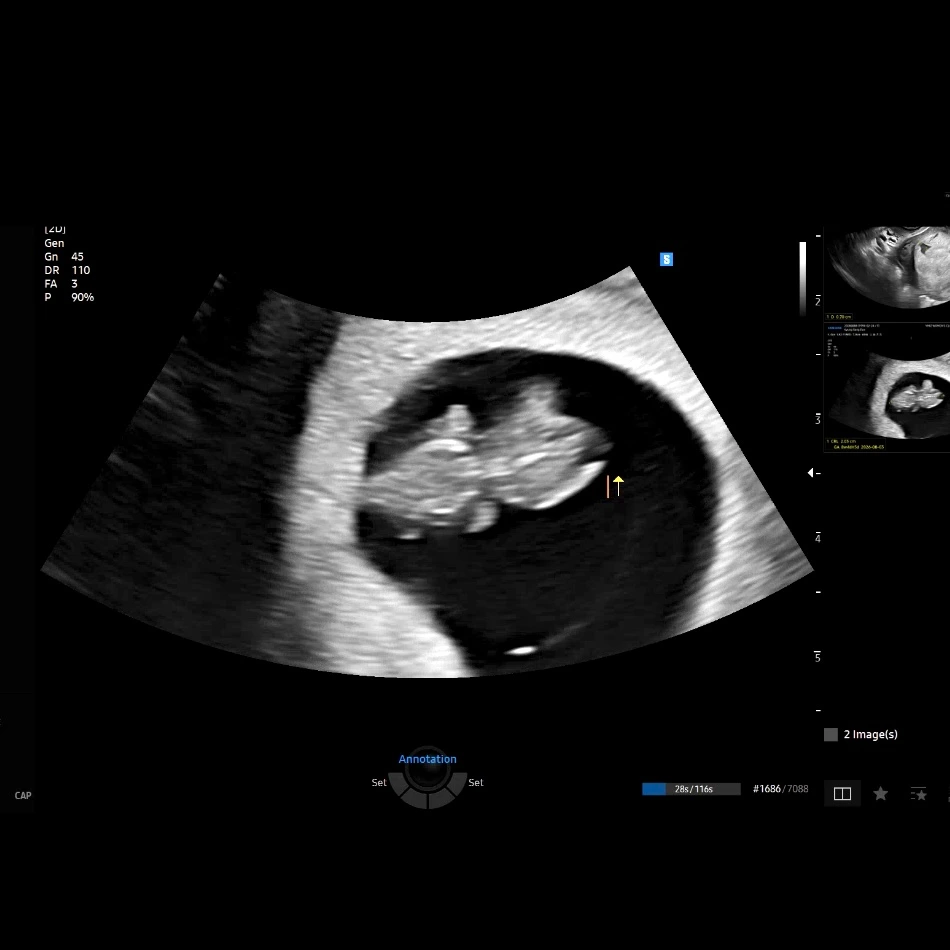

img.png?credential=yqXZFxpELC7KVnFOS48ylbz2pIh7yKj8&expires=1767193199&allow_ip=&allow_referer=&signature=dqW8ao26GVlaxwf%2BO3WelncQZmc%3D 벌써 팔다리가 자라고 있다!

'찹찹이' 아빠가 되다

물론 이 때는 가벼운 마음이었고, '생각을 해보자~ '정도였다. 그런데 감사하게도 그 가벼운 마음을 단번에 꿰뚫고 생명의 축복이 찾아왔다. 아직 10주도 되지 않아 공개가 조심스럽지만 (보통 12주 이후가 안정기라고 한다), 연말이기도 하고 기쁜 소식을 나누고 싶어 조금 이르게 우리 ‘찹찹이’를 소개하게 되었다.

‘찹찹이’라는 태명은 태몽과도 관련이 있고, 우리의 소망을 담은 이름이다. 물건이 차곡차곡 정갈하게 쌓인 모습을 뜻하는 말이기도 하고, 우리 곁에 껌딱지처럼 찹 붙어 있는 모습을 떠올리며 지었다. 어느 날 아내가 꾼 꿈에서, 커다란 갈색 푸들이 자기 몸에 찹 달라붙어 떨어지지 않았다고 한다. 그 모습이 마음에 남아 찹찹이라는 이름이 되었다.